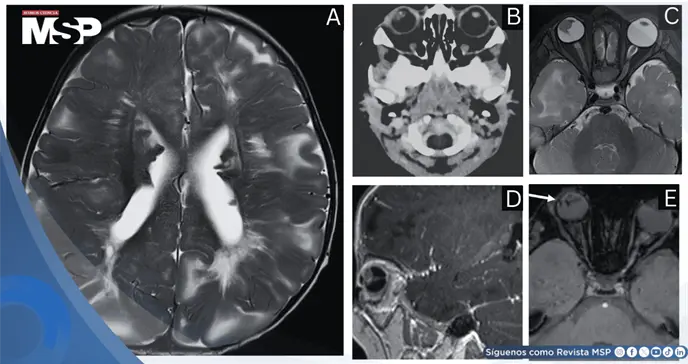

La TC y la RM cerebrales demostraron múltiples nódulos subependimarios en los ventrículos laterales —algunos calcificados— y áreas de baja atenuación subcortical compatibles con túbérculos, hallazgos típicos de TS. En cuanto al globo ocular derecho, la TC reveló microftalmia con una masa de tejido blando adyacente al cristalino y focos de calcificación.

La sin contraste axial de la cabeza de TC muestra microftalmia derecha con una masa de tejido blando asociada con la lente, con un foco de calcificación.

En la RM, la masa se extendía a lo largo del canal de Cloquet hasta el disco óptico. El cristalino derecho era hipotrófico con señal T2 intermedia anómala, y las imágenes ponderadas por susceptibilidad mostraron un artefacto curvilíneo sugestivo de desprendimiento de retina.

Las imágenes ponderadas por susceptibilidad axial cerebral de resonancia magnética demuestran un artefacto de susceptibilidad curvilíneo asociado con la lente derecha, que sugiere desprendimiento de retina.